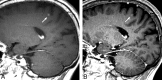

Background and purpose: Early accurate diagnosis of brain metastases is crucial for a patient's prognosis. This study aimed to compare the conspicuity and detectability of small brain metastases between contrast-enhanced 3D fast spin-echo (sampling perfection with application-optimized contrasts by using different flip angle evolutions [SPACE]) and 3D gradient-echo (GE) T1-weighted (magnetization-prepared rapid acquisition of GE [MPRAGE]) images at 3T.

Results: The mean diameter was significantly larger by using SPACE than MPRAGE (mean, 4.5 +/- 3.7 versus 4.3 +/- 3.7 mm, P = .0014). The CR and CNR of SPACE (mean, 57.3 +/- 47.4%, 3.0 +/- 1.9, respectively) were significantly higher than those of MPRAGE (mean, 37.9 +/- 41.2%, 2.6 +/- 2.2; P < .0001, P = .04). The mean area under the ROC curve was significantly larger with SPACE than with MPRAGE (neuroradiologists, 0.99 versus 0.88, P = .013; residents, 0.99 versus 0.78, P = .0001).

Conclusions: Lesion detectability was significantly higher on SPACE than on MPRAGE, irrespective of the experience of the reader in neuroradiology. SPACE should be a promising diagnostic technique for assessing brain metastases.